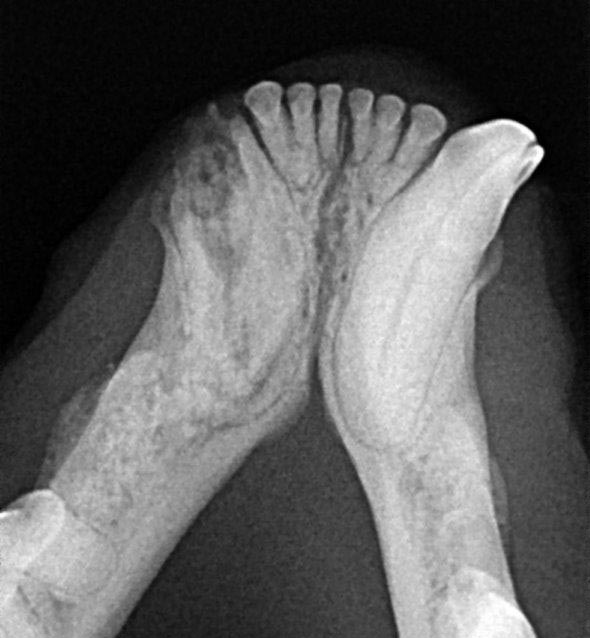

Radiographie Dentaire Numérique

Les radiographies dentaires sont un outil incontournable dans la gestion des traitements bucco-dentaires.

C'est la seule façon d’évaluer la structure de la racine, l’intérieur de la dent et l’os supportant la dent car les 2/3 de sa hauteur se situe sous les gencives.

Pour effectuer cet examen nous utilisons un appareil de radiographie dentaire numérique équipé d’ un capteur qui se met directement dans la bouche de l’animal.